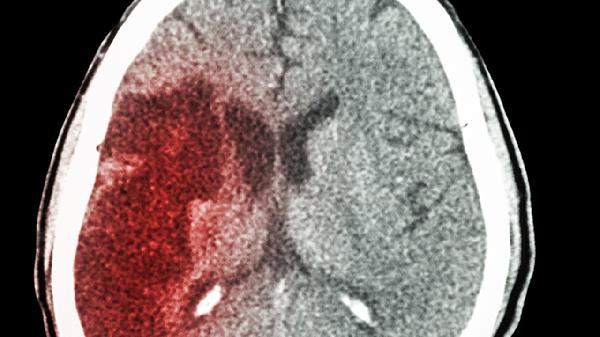

脑梗后遗症怎么识别和判断

脑梗后遗症的表现形式多样,包括肢体运动障碍、语言表达困难、认知功能下降、吞咽问题以及情绪波动等。这些症状通常源于脑组织因缺血而坏死,进而影响神经功能,需通过影像学检查和临床表现综合判断。

脑梗后遗症患者日常应保持低盐低脂饮食,每天注意监测血压和血糖水平。康复训练要循序渐进,上肢可以尝试抓毛巾练习,下肢则可做床边踏步动作。家属应帮助记录患者的症状变化,定期复查头颅CT观察恢复情况。一旦出现发热、肢体肿胀等新症状,应及时就医处理。